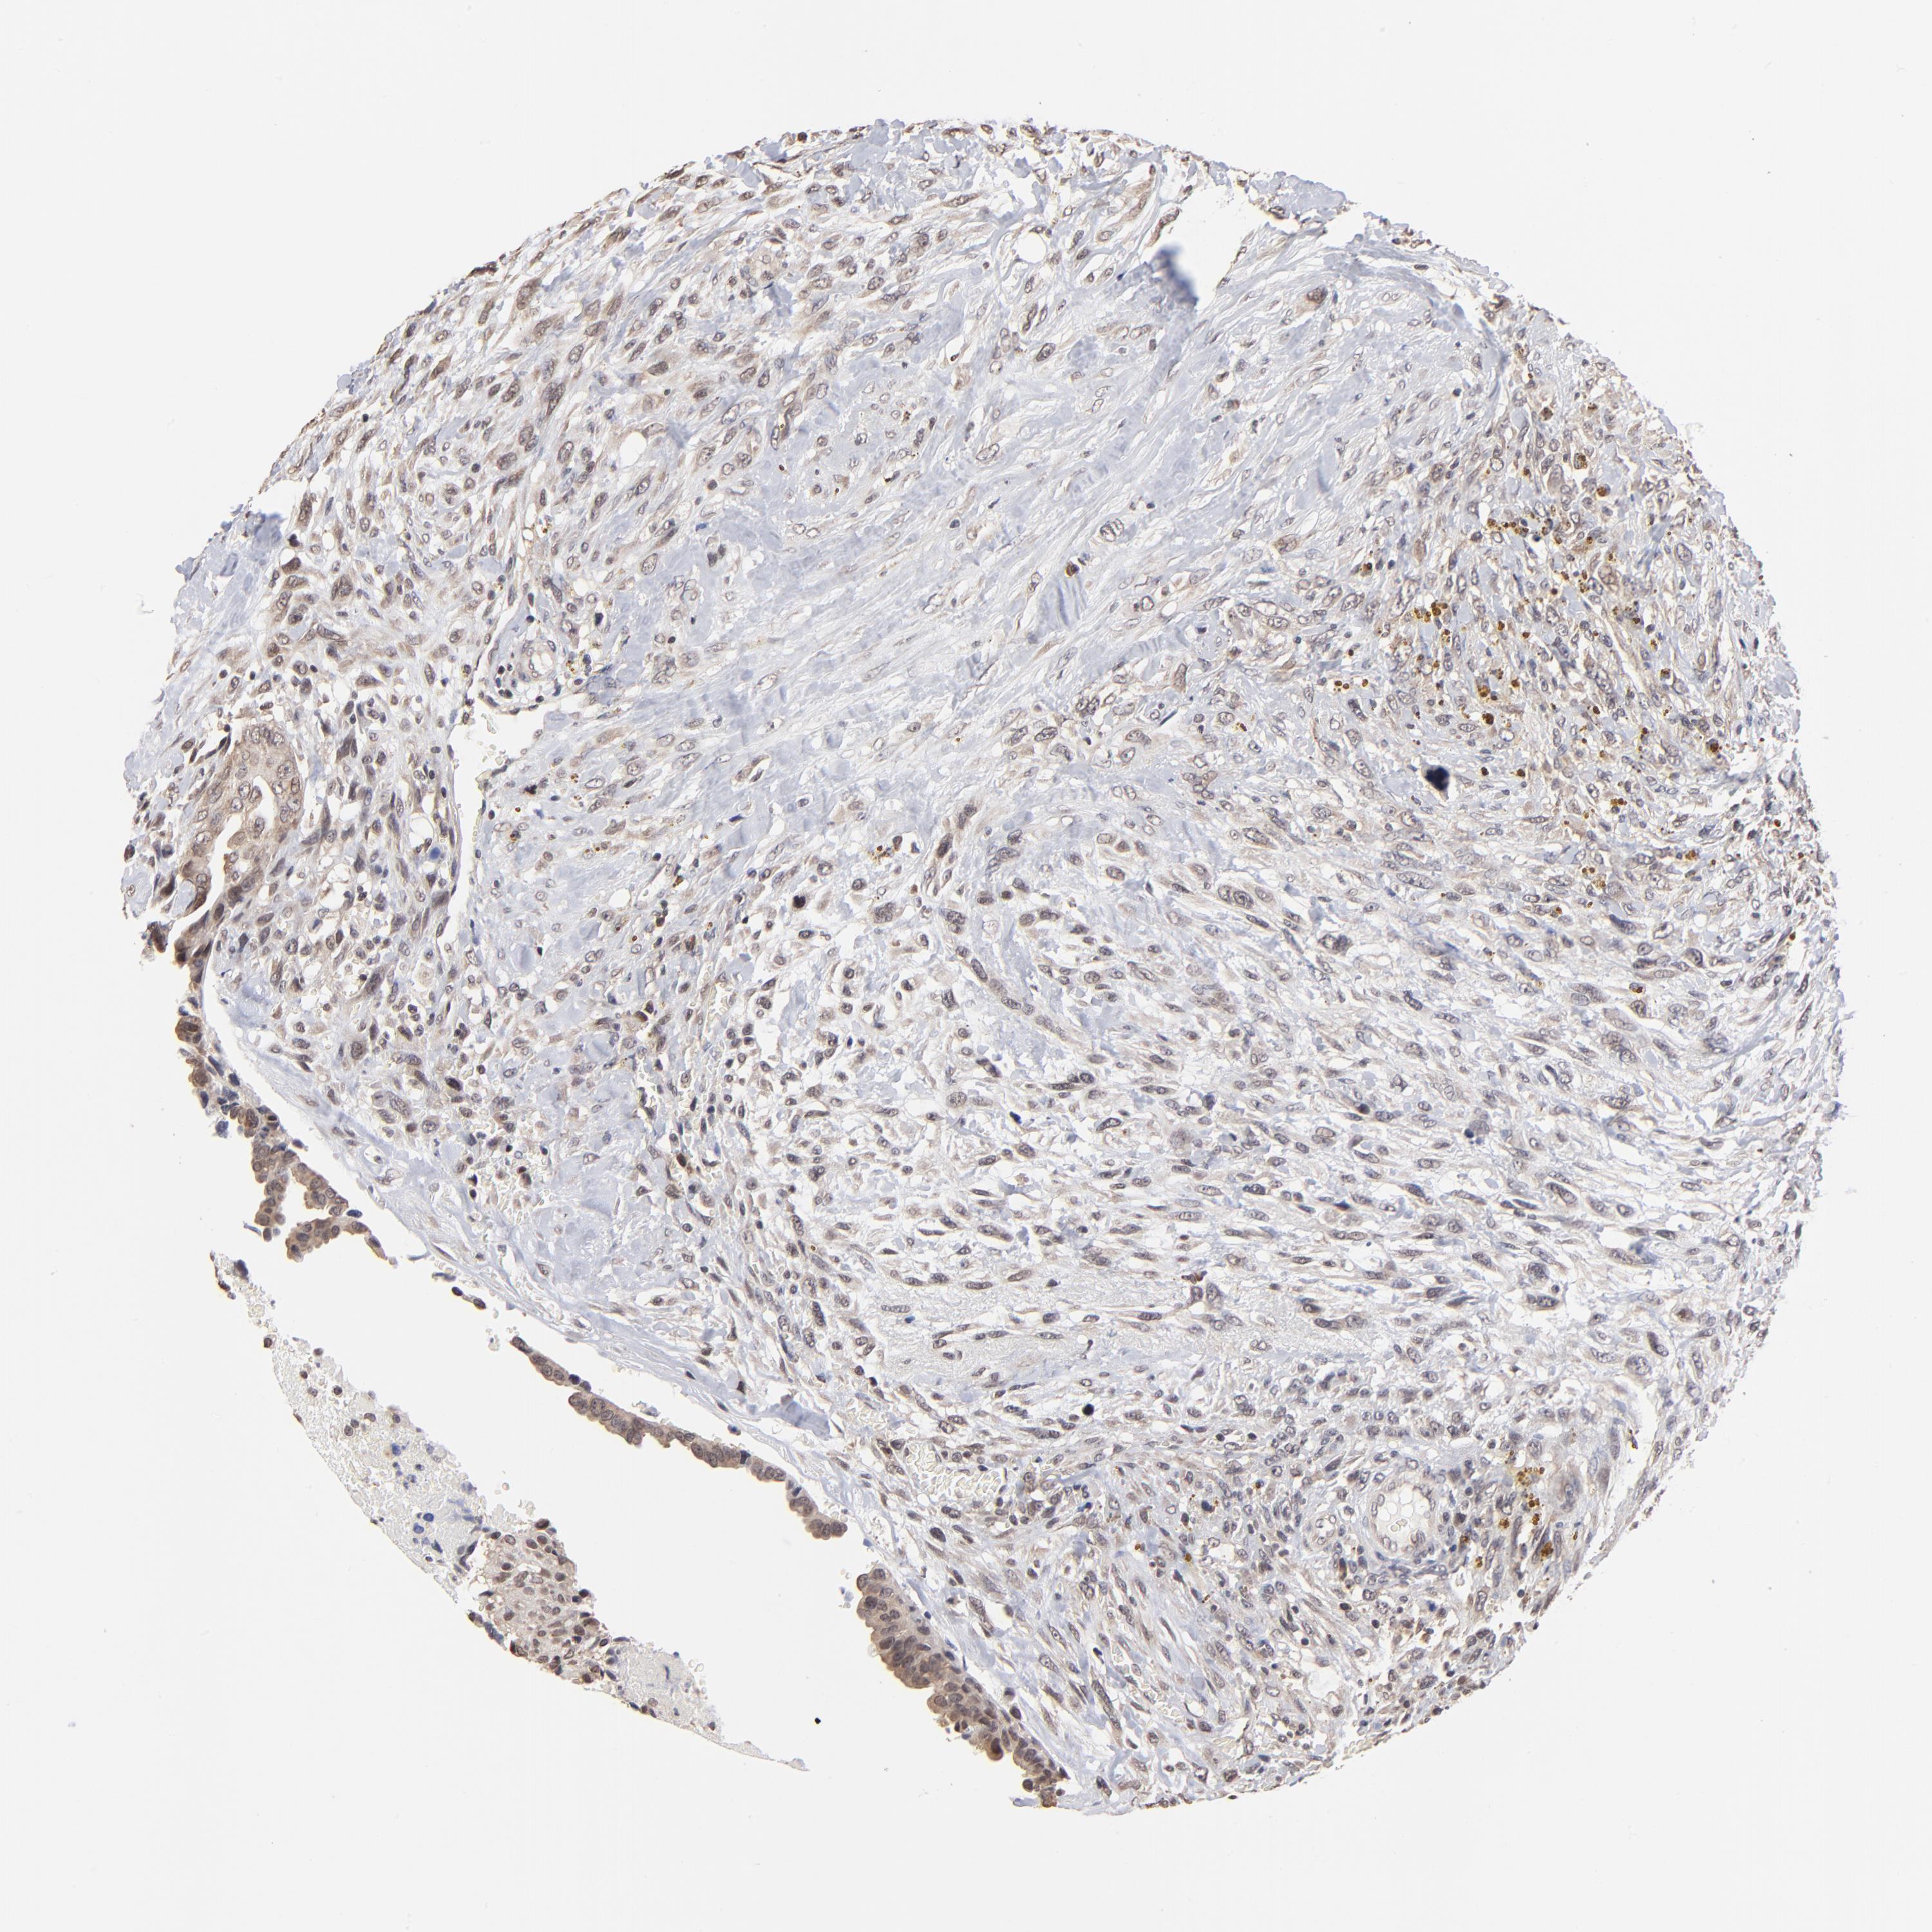

CANCER BREAST CANCER Show tissue menu

BRCA TCGA BRCA VALIDATION PROTEIN EXPRESSION

ANTIBODIES

AND

VALIDATION